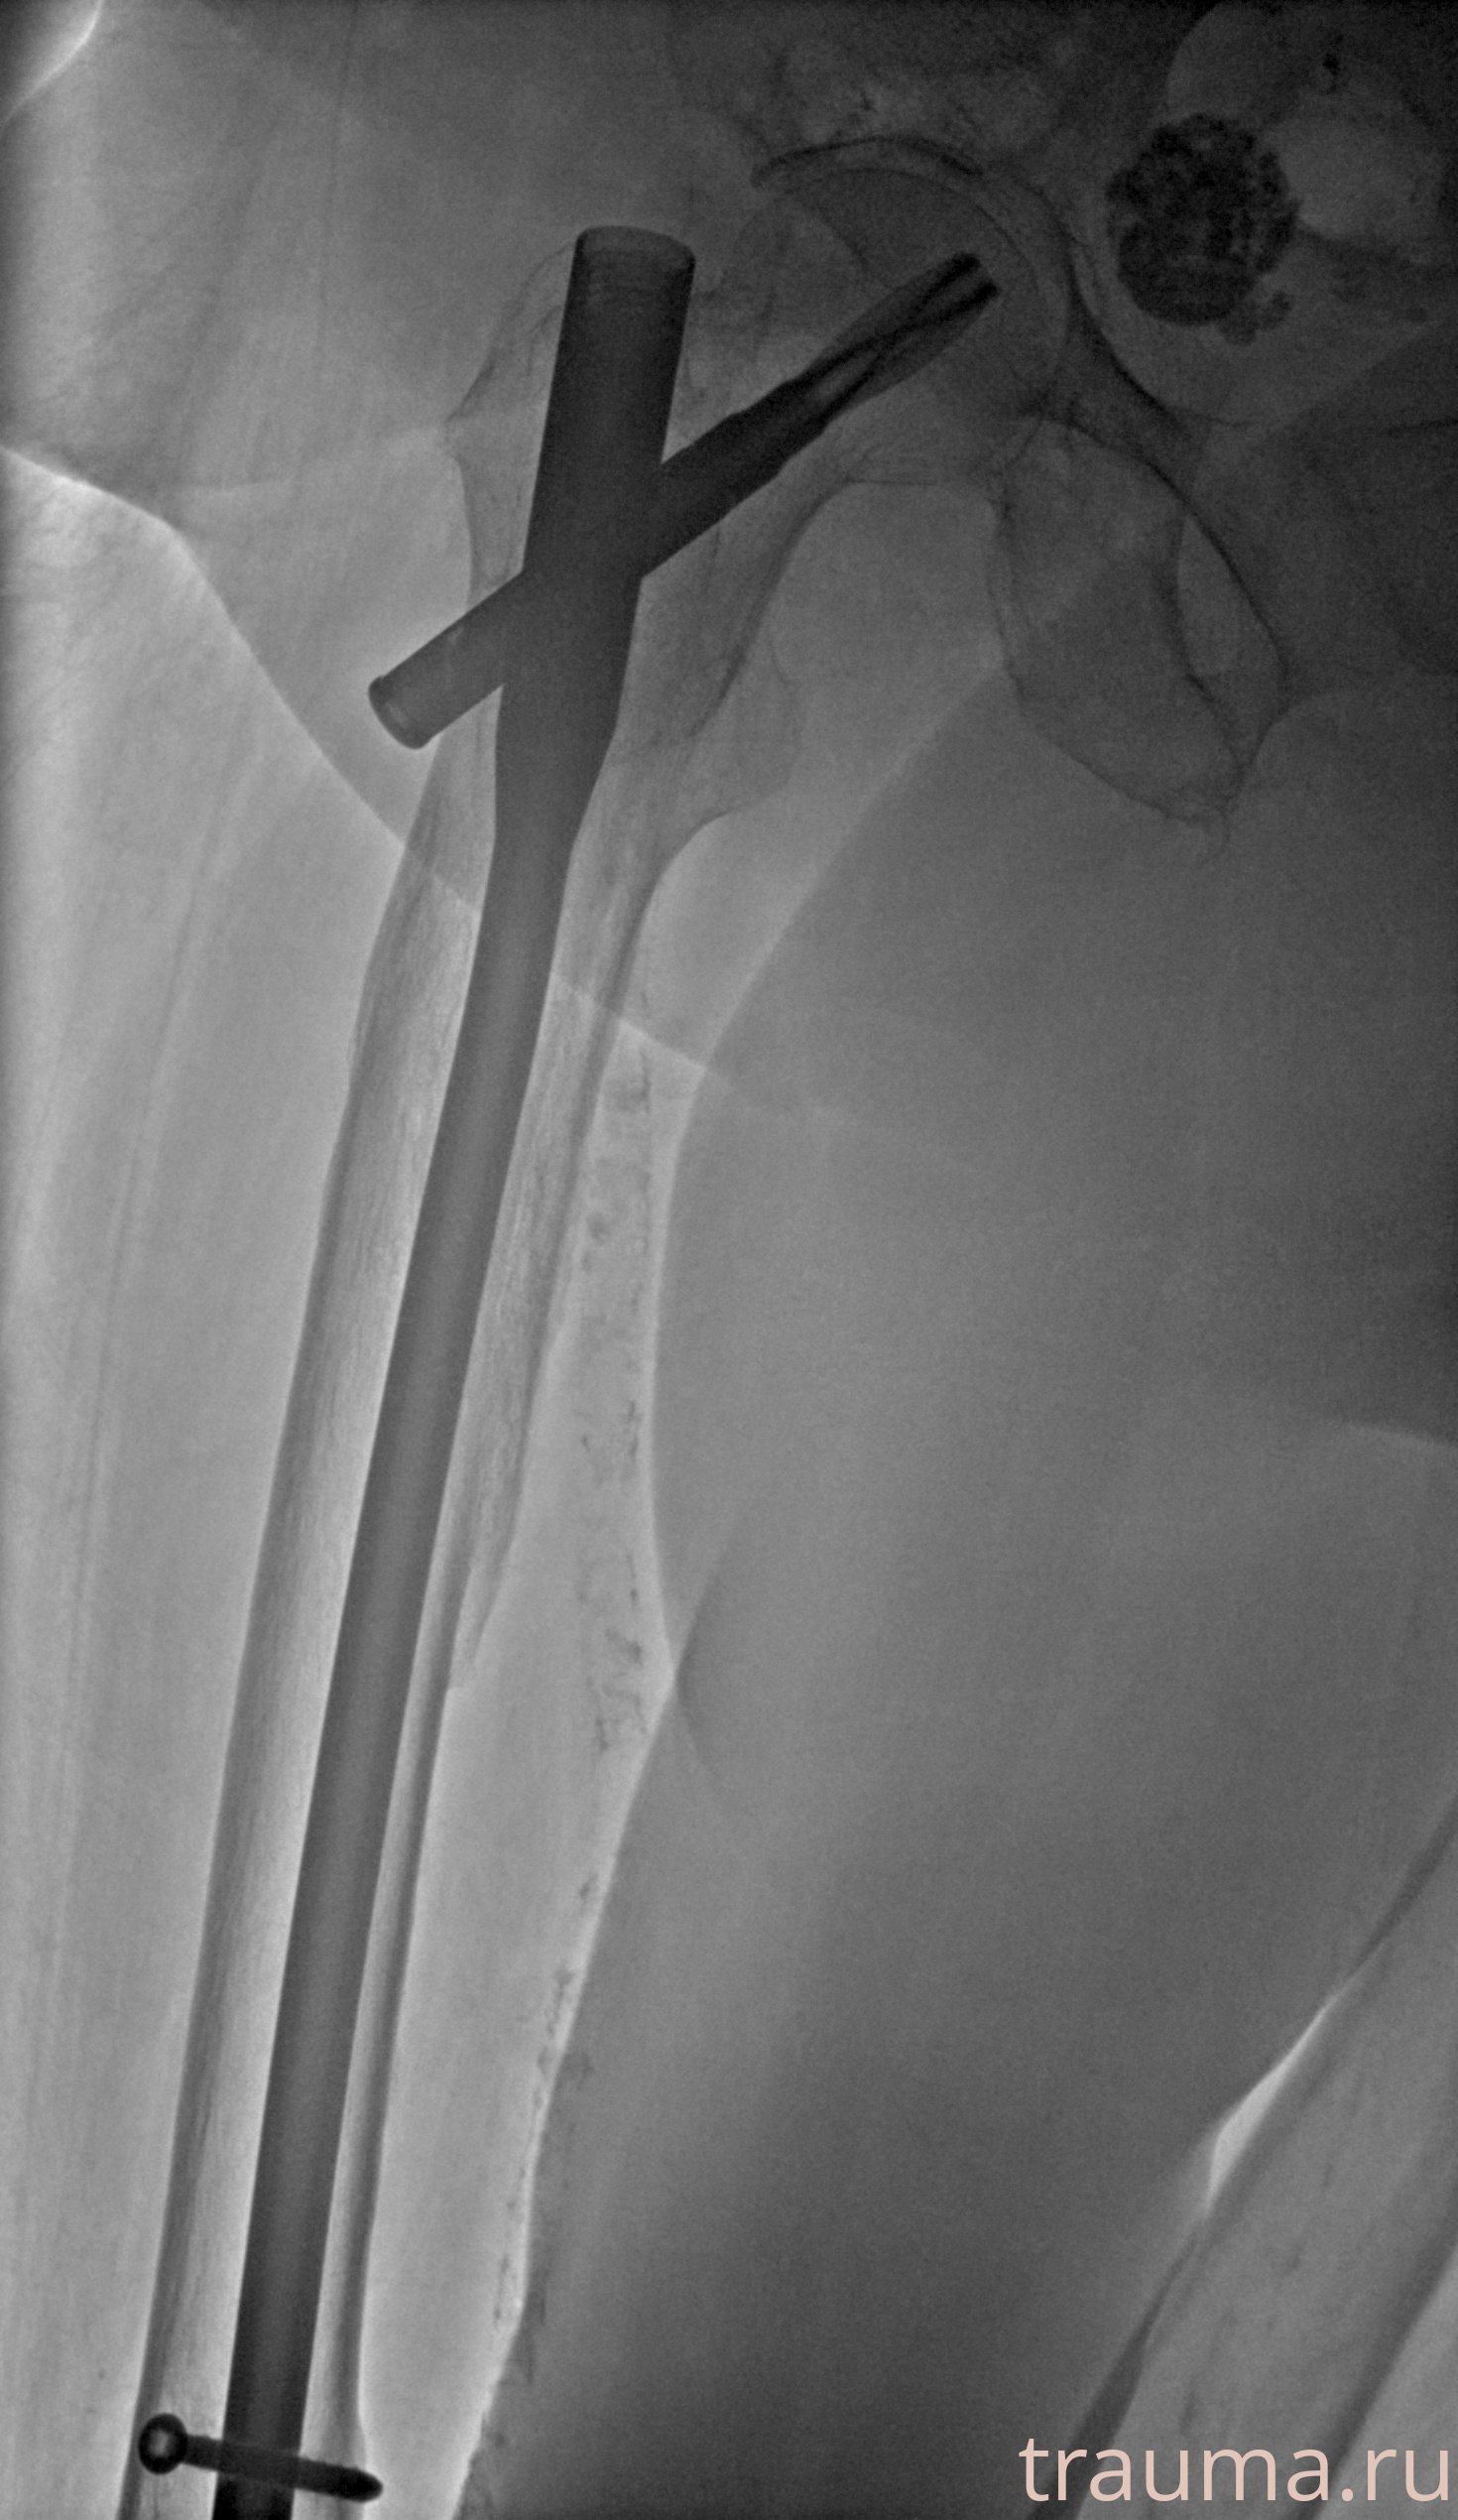

Рентгенограммы